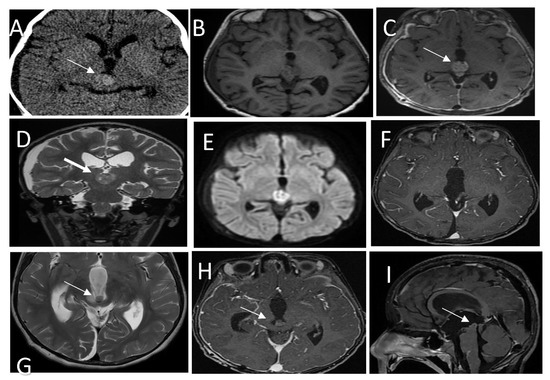

Figure 3.

(A) CT scan shows a hyperdense pineal gland mass with no calcification (arrow). (B) SE T1W MRI shows an isointense lesion with peripheral areas of hyperintensity. (C) Post-contrast T1W MRI shows enhancement of the lesion (arrow). (D) T2WI in coronal plan shows a low signal intensity behavioral appearance of the lesion. (E) Diffusion weighted images show bright signal indication diffusion restriction (ADC not shown) (F) Post-contrast T1W MRI after the first resection shows gross total resection. (G) Follow-up MRI T2 WI shows a recurrent lesion in the posterior inferior aspect of the third ventricle (arrow) with mass effect. (H,I) Post contrast T1W MRI in axial and sagittal shows the recurrent lesion. Histologic features of the tumor assessed by routine hematoxylin and eosin staining demonstrate (J) a mainly solid growth pattern with round-oval nuclei and abundant clear cytoplasm and (K) short columnar perivascular cells with clear cytoplasm. (L) DNA methylation class PTPR Group A.

Histopathology analysis revealed a PTPR (Figure 3J,K) with papillary infiltrates showing necrotic foci and a moderate proliferative index and absence of mitotic activity.

Methylation class analysis identified a papillary tumor of the pineal region group B (Figure 3L). CSF cytology showed inflammatory cells. No malignant cells were detected (not shown).

A brain MRI showed a recurrent pineal region tumor measuring 0.9 × 0.9 × 0.7 cm3 in AP, TR, and CC, respectively. The lesion was situated in the posterior aspect of the third ventricle and embedded in the proximal cerebral aqueduct, causing secondary obstructive hydrocephalus with a mass effect on the tectum, which was displaced posteriorly (Figure 3G–I); MRI of the spine was unremarkable (not shown).